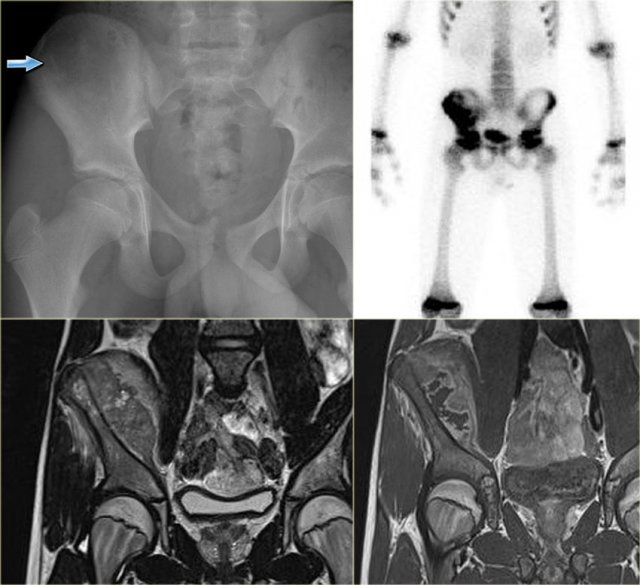

Ewing sarcoma Ewing sarcoma

Ewing sarcoma (3)

On the left images of a large lytic tumor arising from the right iliac bone.

On the plain film it is very hard to appreciate the lesion because of the permeative destruction pattern.

Scintigraphy shows extensive uptake within the iliac bone.

Sometimes, a cold spot is found in Ewing sarcoma.

MR reveals the intra- and extraosseous tumor extension.